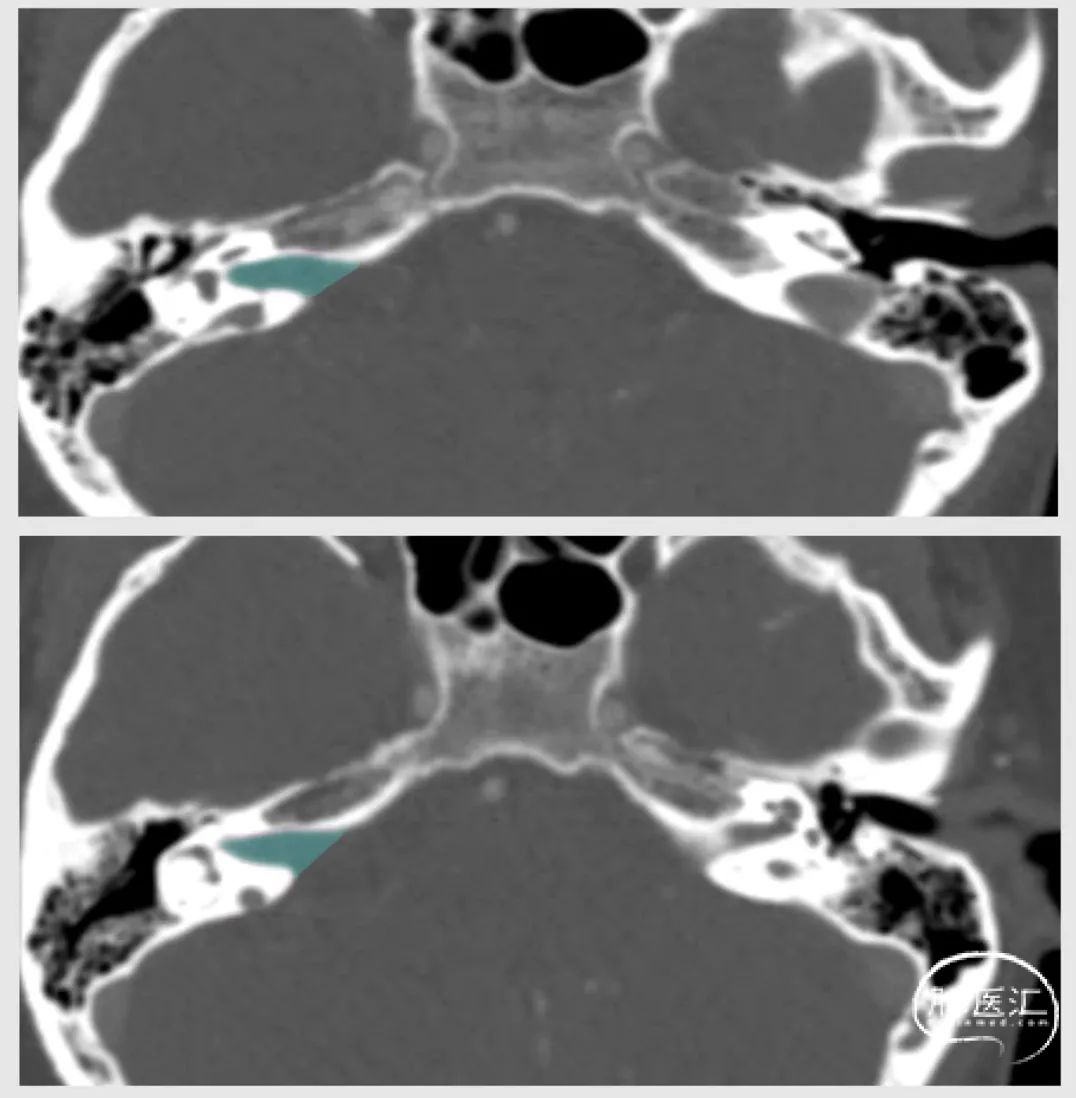

患者术前CT 【显示患侧内听道扩大】

患者术前颈静脉球【高位】